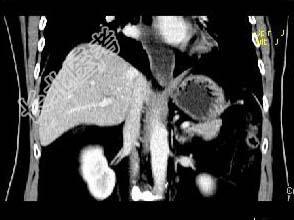

- 单项选择题根据所提供的图像,最可能的诊断是 ( )

A、肝血管瘤

B、局灶性结节增生

C、肝硬化再生结节

D、肝癌

E、肝转移癌